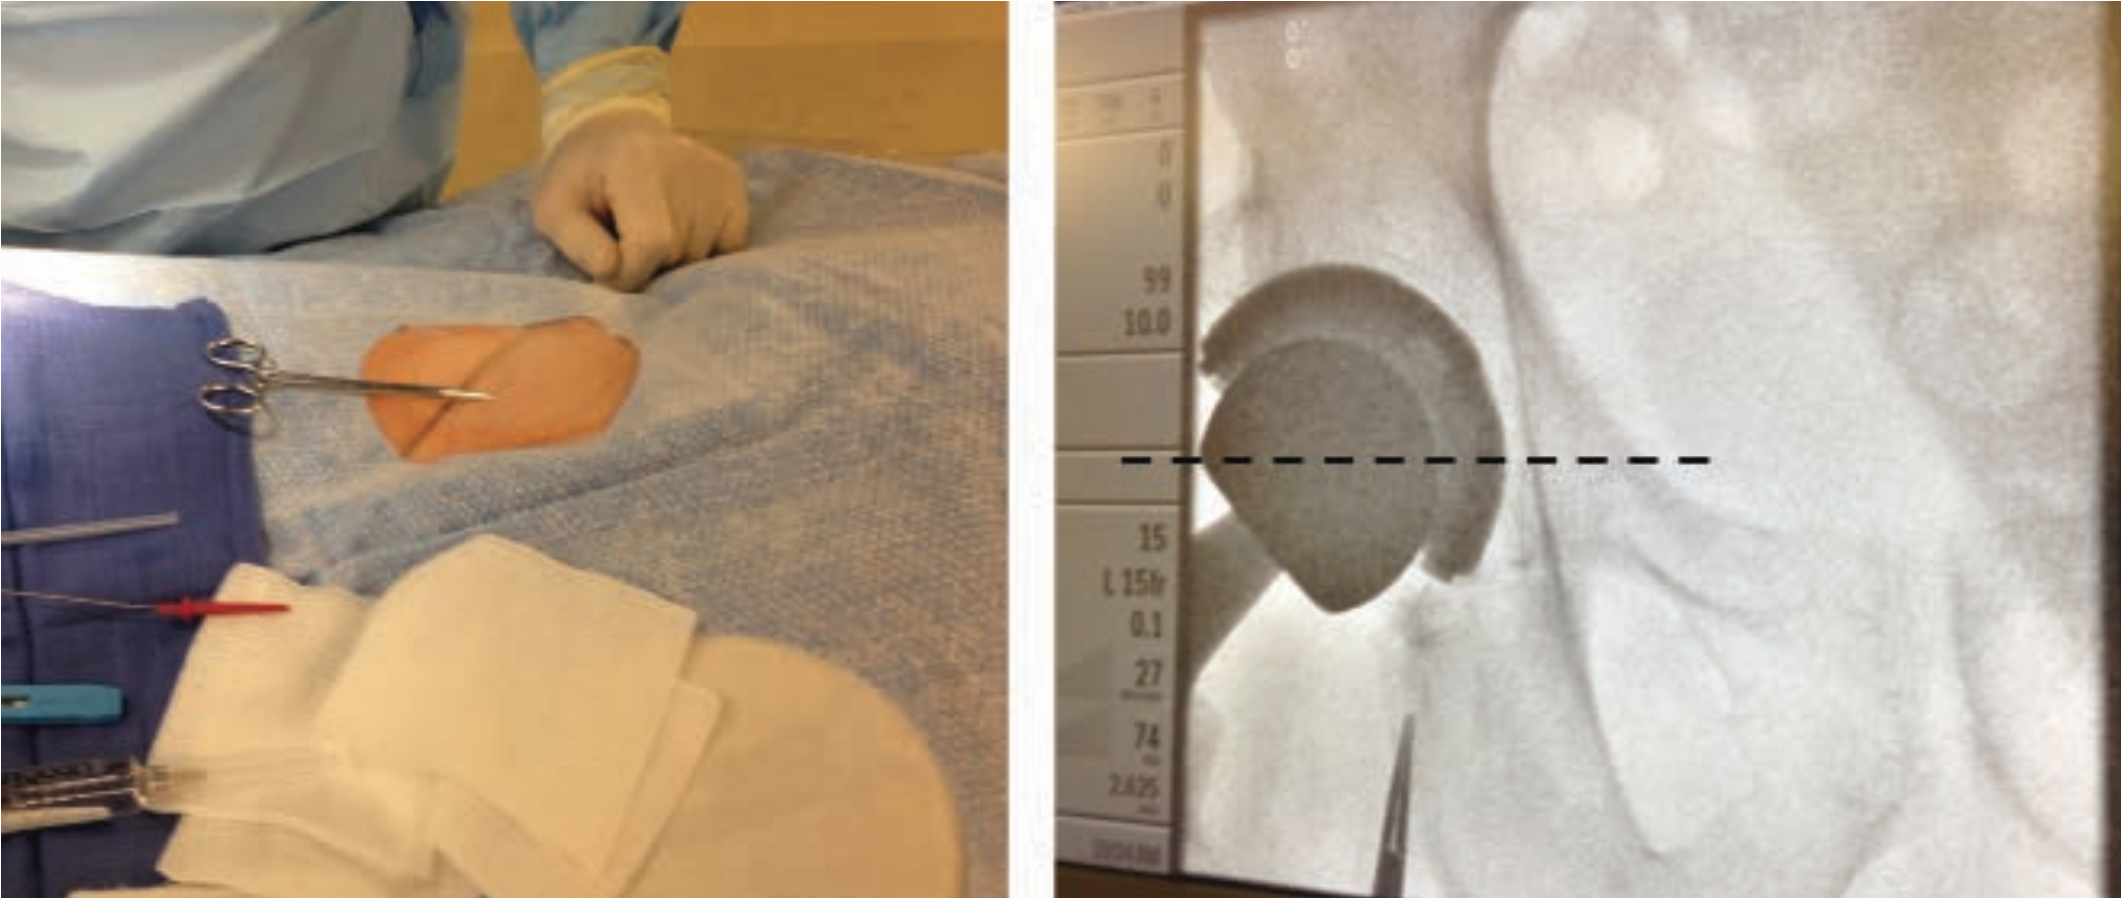

For improved accuracy, place a metal clamp over the proposed entry site and perform a quick fluoro exam to confirm the relationship of the clamp to the femoral head (Figure 3). The needle can then be positioned slightly more caudal or cranial for best puncture. By angling about 30 degrees from the horizontal, the needle will enter the artery higher than the skin entry site.